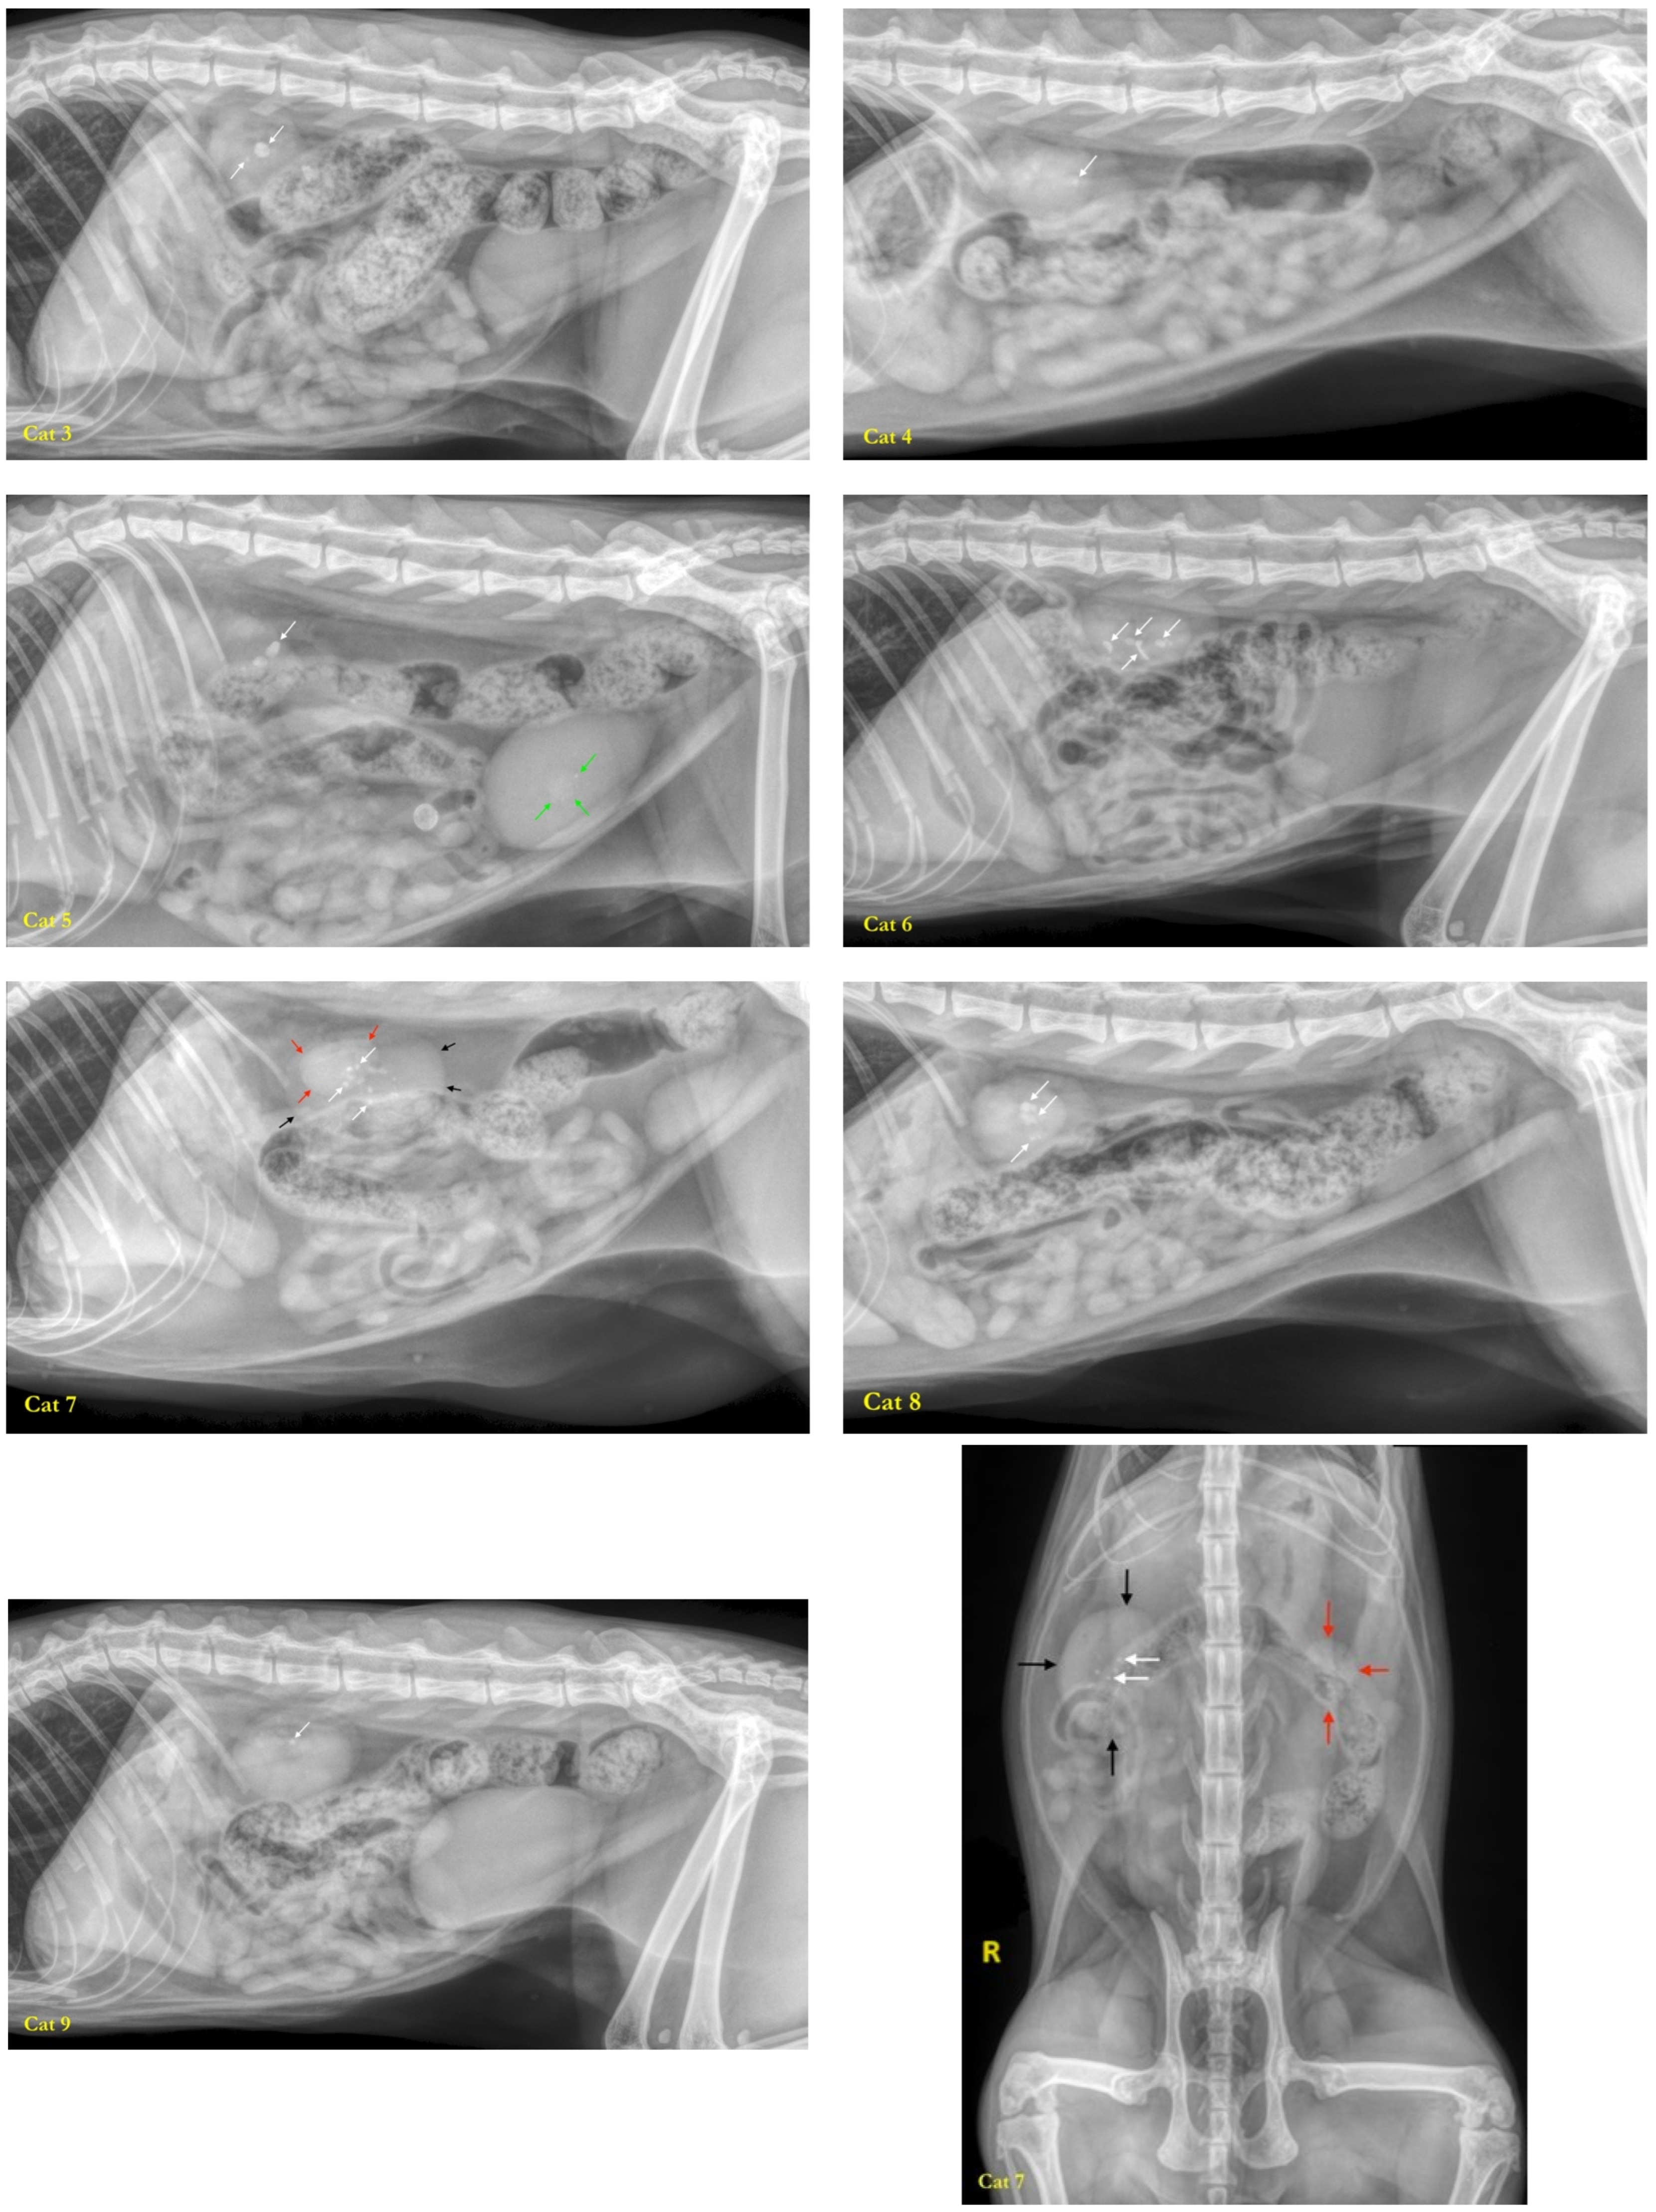

3.1. Studied Population

3.2. Characterization of the Fecal Microbiota